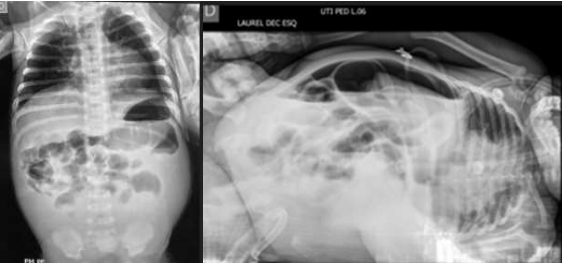

Lactente jovem internado há alguns dias, em Unidade Pediátrica, evoluindo durante o internamento com

importante distensão abdominal. Solicitado RX em pé e em decúbito lateral (imagens abaixo).

Qual dos contextos clínicos listados abaixo melhor explica os achados radiológicos encontrados?